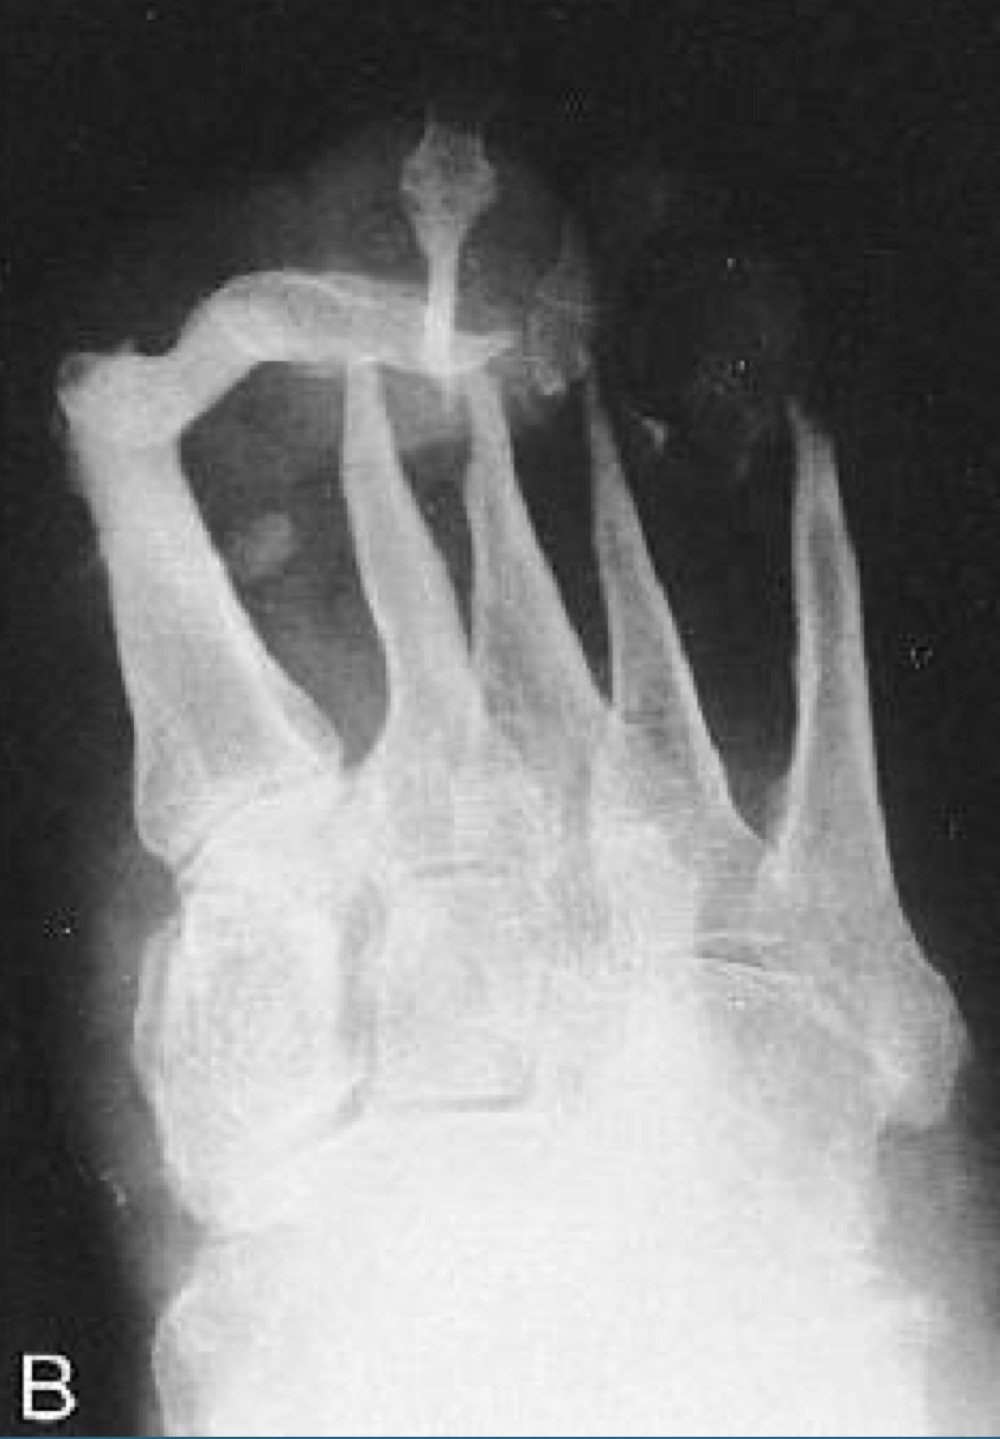

what finding is in this image

hypertrophic neuropathic arthropathy

what is the finding in this image? AKA

neuropathic arthropathy AKA charcot’s joint

atrophic neuropathic arthropathy

what appearance does atrophic neuropathic arthropathy typically take on ?

licked candy stick

what would this charcot joint be caused by

syphilis

syringomyelia

diabetes